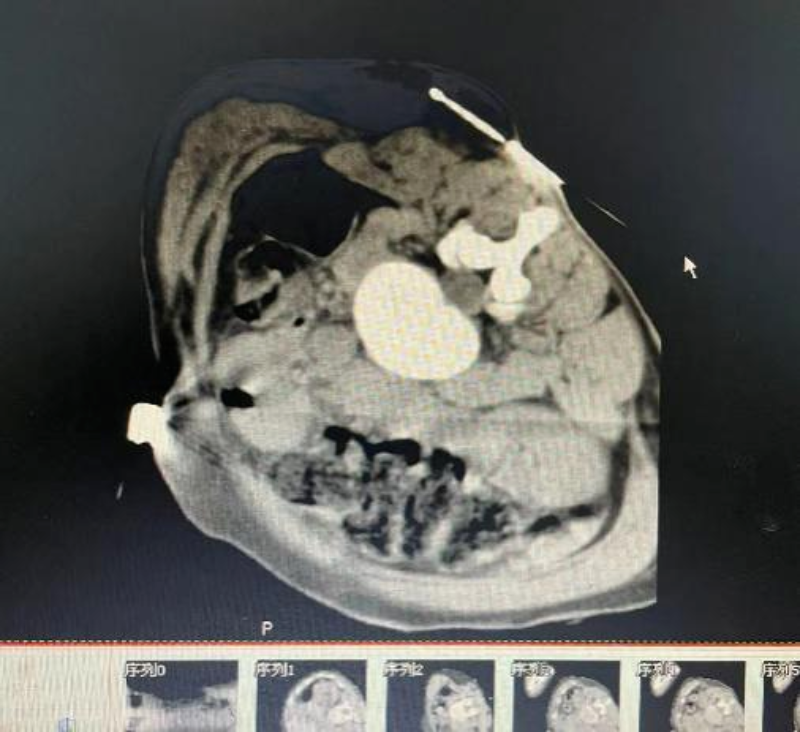

近期,50歲的陳女士(化名)因左肺癌綜合治療后復發1年,全身疼痛半年有余,止痛藥已經無法幫助張女士緩解疼痛癥狀,家屬便將其送往我院腫瘤科。在此之前,她的家人帶著她輾轉于多家醫院就診,而得到的回應只有一句句抱歉。我院腫瘤科醫生團隊認真分析患者的病例,針對手術必要性、風險、方式逐一分析討論,在征得患者及其家屬同意后,最終決定采用“氬氦刀冷凍消融術”對張女士的肺部腫瘤進行冷凍消融,使腫瘤細胞冷凍壞死,起到減瘤緩解疼痛的目的。

局麻后,我院腫瘤科醫護團隊在CT定位引導下,確認穿刺點及穿刺路線,將冷凍針精準穿刺到位,實施冷凍消融,直至冷凍范圍完全覆蓋病灶,摧毀腫瘤細胞組織。手術非常成功,患者術后無不適癥狀,不久后即可進食并適當活動。

冷凍消融前。